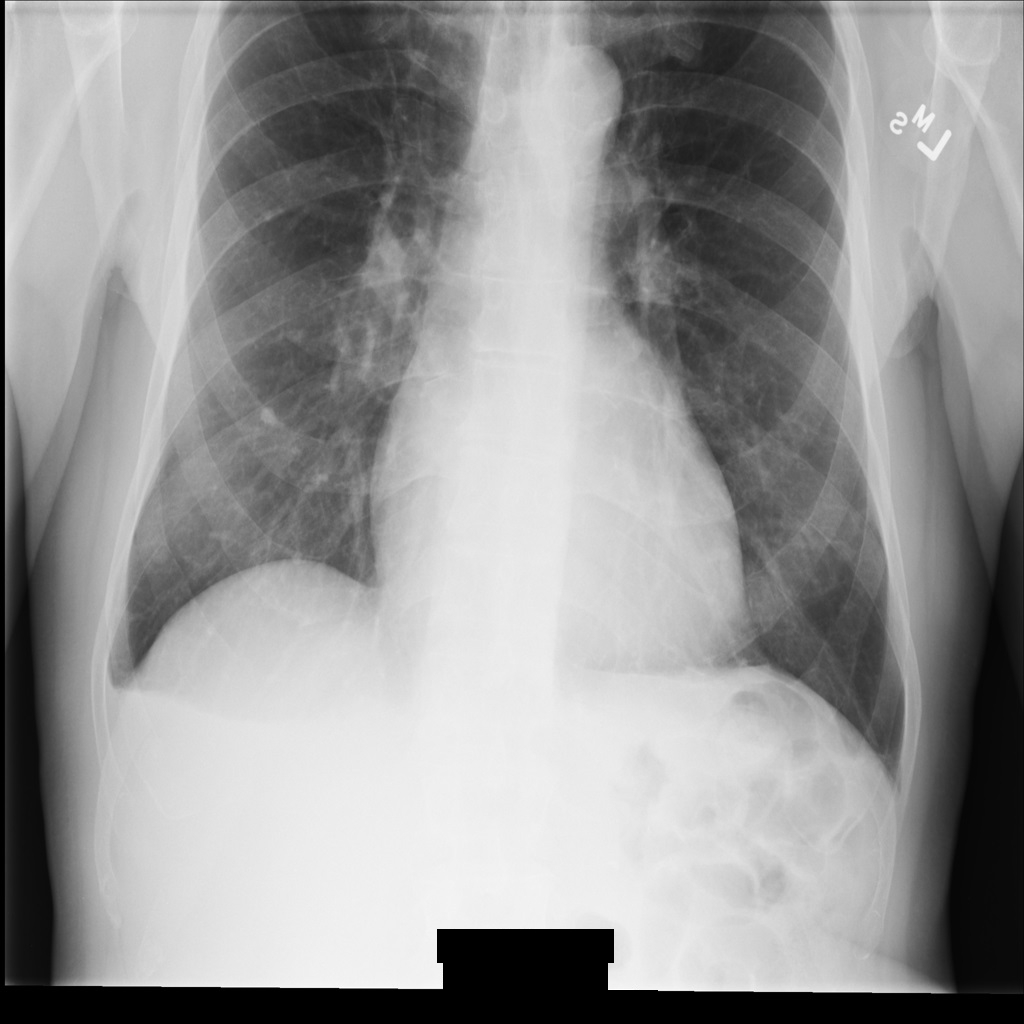

Beispielbild

Einige Beispiele auf dieser Seite enthalten eine Ausgabe des de-identifizierten Bildes. In jedem Beispiel wird das folgende Originalbild als Eingabe verwendet. Sie können das Ausgabebild jedes De-Identifizierungsvorgangs mit diesem Originalbild vergleichen, um die Auswirkungen des Vorgangs zu sehen:

Nach der De-Identifikation des Bildes mit REDACT_ALL_TEXT sieht es so aus. Beachten Sie, dass der gesamte eingebrannte Text am unteren Rand des Bildes entfernt wurde.

Nach der De-Identifikation des Bildes mit REDACT_SENSITIVE_TEXT_CLEAN_DESCRIPTORS sieht es so aus. Beachten Sie, dass nicht der gesamte eingebrannte Text am unteren Rand des Bildes entfernt wurde. Der Text Female wird weiterhin angezeigt, da PatientSex (0010,0040) nicht zu den Standard-DICOM-infoTypes gehört.